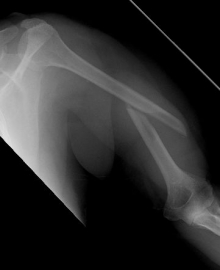

Proximaler Oberarmbruch5Proximaler Oberarmbruch6

Picture: Here is a subcapital upper arm break in a young woman. An angle stable plate osteosynthesis was performed to stabilize the head in correct position to the humeral shaft and shoulder joint. Especially in young patients, We strive to treat non-invasively and as gently as possible. This possibility is often due to the bone quality in young as opposed to older people.